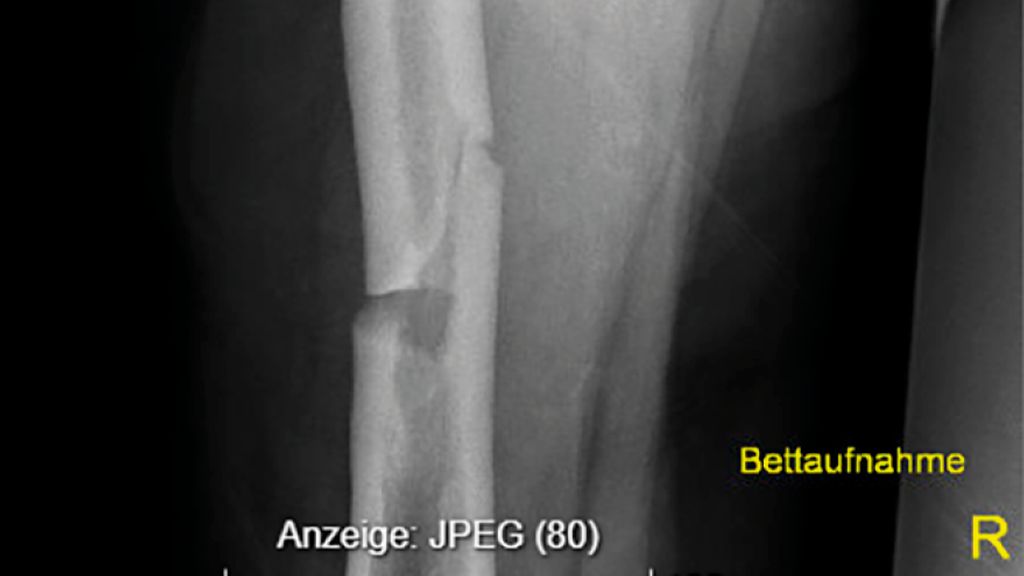

Eine Analyse der Femurfraktur in der Anamnese zeigte, dass es sich dabei um keine typische osteoporotische Fraktur am Femurhals, sondern um eine atypische Fraktur am Femurschaft unter Bisphosphonattherapie gehandelt hatte, wofür eine gerade Frakturlinie auf der lateralen und eine schräge Frakturlinie auf der medialen Seite sprachen (Abb.1).1 Der Fraktur waren keine Schmerzen vorausgegangen; diese gelten als Warnsignal für atypische Frakturen.2 Werden Patient:innen unter antiresorptiver Therapie mit unbestimmten Knochenschmerzen an den Oberschenkeln vorstellig, so sollte man hellhörig werden, erläuterte Rintelen.

Abb. 1: Die Röntgenaufnahmen zeigen eine atypische gerade Frakturlinie auf der lateralen und eine schräge Frakturlinie auf der medialen Seite